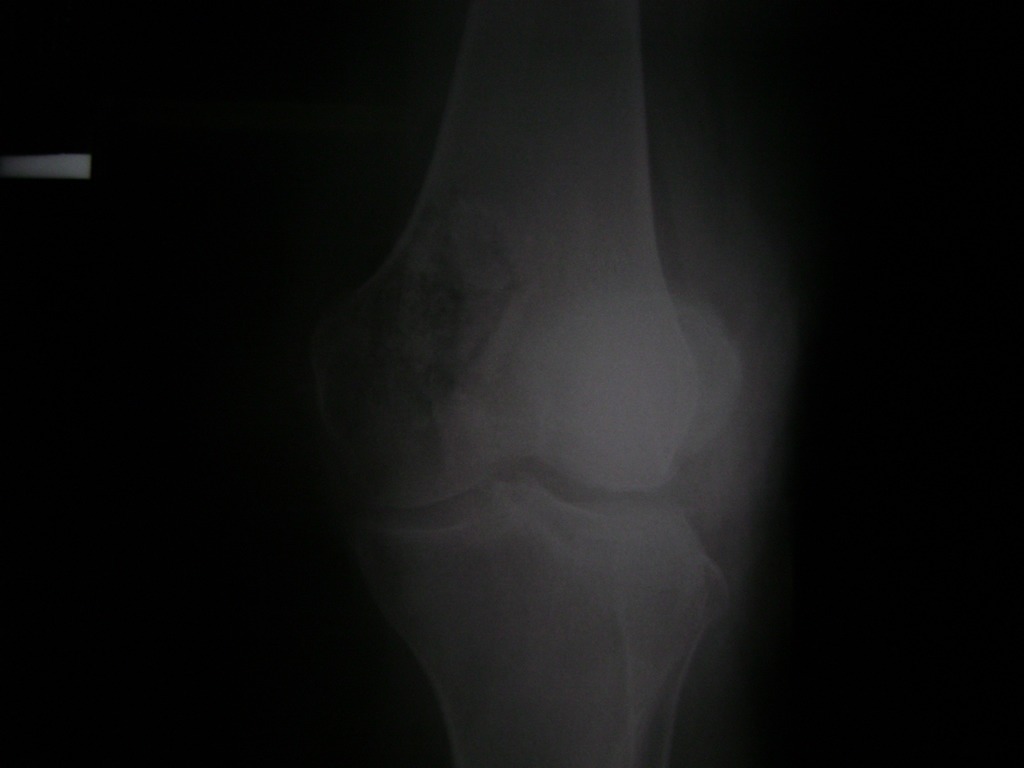

La artroscopia de rodilla es un cirugía en el cual la estructura interna de la articulación es examinada ya sea para realizar un diagnostico o para realizar un tratamiento, este procedimiento se realiza utilizando un instrumento parecido a un pequeño tubo llamado artroscopio.

La artroscopia se popularizo en 1960 y hoy en día es muy común en todo el mundo. Típicamente, es realizada por cirujanos ortopédicos de manera ambulatoria. Cuando se realiza de manera ambulatoria los pacientes pueden regresar a casa después de la operación, no se requiere quedarse en hospital.